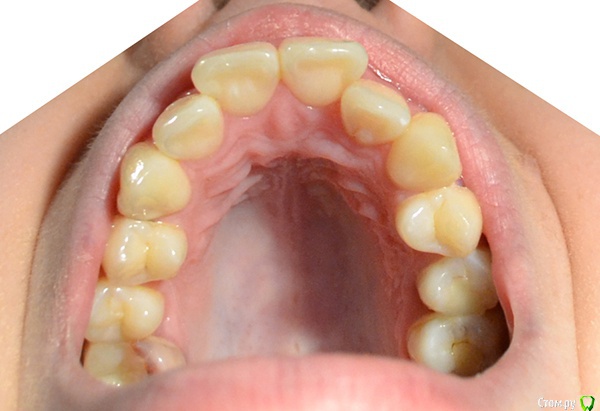

Мне 22 года, планирую исправить проблемы с прикусом, сейчас ищу информацию, рассматриваю варианты.

Очень нужен совет - действительно ли в моем случае лучшим выбором будет удаление 4ок на обеих челюстях?

Консультировалась у двух ортодонтов, оба сказали: без вариантов, зубы крупные, места не хватает.

В общем, прилагаю фото, подскажите, пожалуйста, что можно с этим сделать.